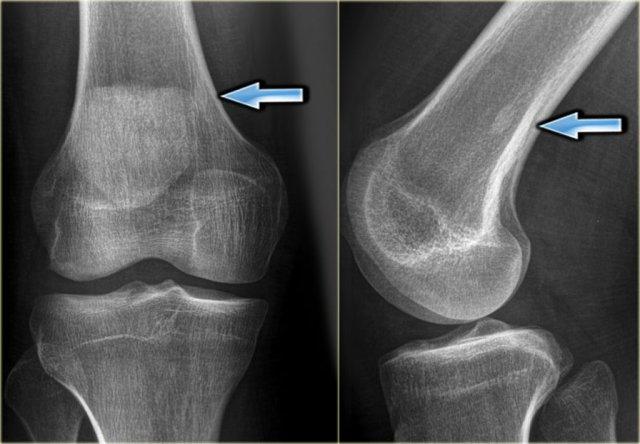

Đây là hình ảnh của một bệnh nhân có khối xơ cứng cạnh vỏ xương ở đầu trên xương cánh tay (trái).

Trường hợp này được xác định là vôi hóa phản ứng thứ phát sau chấn thương.

Lưu ý sự tương đồng với khối u cạnh vỏ xương ở một bệnh nhân khác (bên phải), được chẩn đoán xác định bằng sinh thiết là u xương cạnh màng xương (parosteal osteosarcoma).

Điều này cho thấy rằng việc phân biệt khối u với một quá trình phản ứng đôi khi có thể rất khó khăn trong một số trường hợp.

Khi một quá trình phản ứng có khả năng xảy ra hơn dựa trên tiền sử và đặc điểm hình ảnh, đôi khi vẫn cần theo dõi thêm.